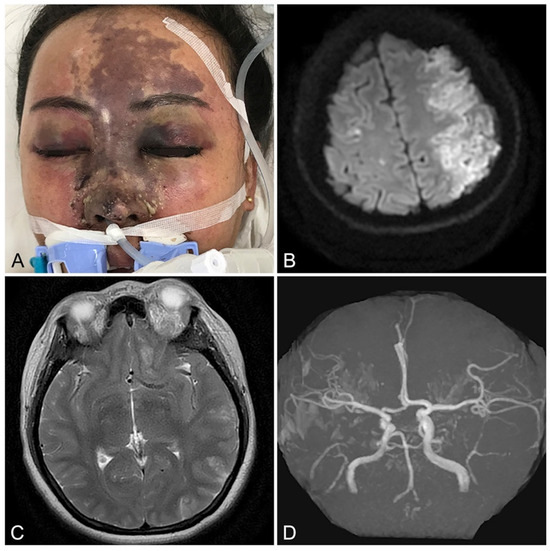

- Yang, Q.; Lu, B.; Guo, N.; Li, L.; Wang, Y.; Ma, X.; Su, Y. Fatal Cerebral Infarction and Ophthalmic Artery Occlusion After Nasal Augmentation with Hyaluronic Acid-A Case Report and Review of Literature. Aesthetic Plast. Surg. 2020, 44, 543–548. [Google Scholar] [CrossRef]

- Zhao, F.; Chen, Y.; He, D.; You, X.; Xu, Y. Disastrous cerebral and ocular vascular complications after cosmetic facial filler injections: A retrospective case series study. Sci. Rep. 2024, 14, 3495. [Google Scholar] [CrossRef]

- Wang, H.C.; Yu, N.; Wang, X.; Dong, R.; Long, X.; Feng, X.; Li, J.; Wu, W.T.L. Cerebral Embolism as a Result of Facial Filler Injections: A Literature Review. Aesthetic. Surg. J. 2022, 42, NP162–NP175. [Google Scholar] [CrossRef]